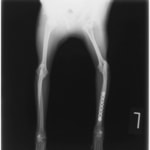

ペルシャ猫 11ヶ月齢 雄

他院にて左大腿骨遠位の成長板骨折(salter-harrisⅠ型)が認められており、治療相談を目的として来院。当院にて、キルシュナーワイヤーを用いたピンニングにより骨折部位の整復を行いました。術後の経過は良好で、現在も経過観察中です。

術後レントゲン

Arthrex社のターゲティングデバイスを用いてピンニングの位置を調整することで、確実な固定を行っています。当院ではこの手術器具以外にも、人の手術にも使用される様々な器具を導入し、手術精度を高め、また医療メーカーと新しい器具の開発、試作にも取り組んでおります。